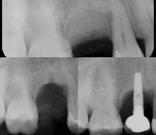

Cirujano dentista con especialidad en periodoncia e implantes dentales. Posee un fellowship oral. Miembro del Colegio de Cirujanos Dentistas de Puerto Rico y del American Association of Periodontology. Presidente de la Asociación de Periodoncistas de Puerto Rico.

La doctora Frances M. Herrero se graduó Magna Cum Laude de Bachillerato en Ciencias del Colegio de Mayagüez y Suma Cum Laude del Recinto de Ciencias Médicas, Escuela de Medicina Dental. Especialidad en Periodoncia de la Universidad de Maryland. Pertenece al Colegio de Cirujanos Dentistas; Sociedad de Especialistas en Periodoncia e Implantología de Puerto Rico, Sociedad Americana de Periodoncia y es Board eligible en Periodoncia.

Comenzó su trayectoria académica en la UPR de Mayagilez, donde obtuvo su Bachillerato en Biología. Luego continuó sus estudios en la Escuela de Medicina Dental de la Universidad de Puerto Rico de Ciencias Medicas, graduándose con su título de Doctor en Medicina Dental (DMD) en 2013. El Dr. Reinaldo Deliz Guzman está profundamente comprometido con la excelencia en la atención periodontal y se enorgullece de servir, a la comunidad local en PR,

Infección en Implantes